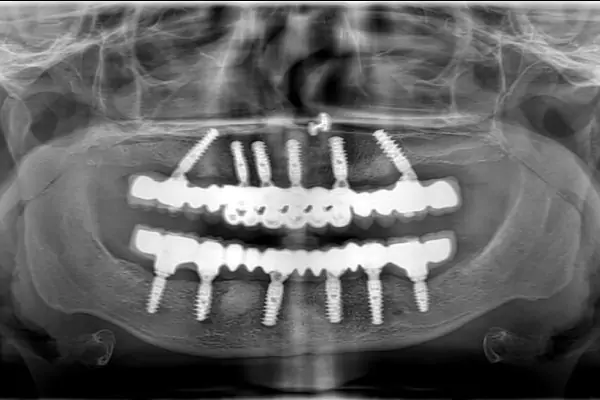

Full Mouth Implants

Get a full arch restored using 4–6 implants for permanent teeth replacement.

Fullmouth

When it comes to improving the condition of your teeth, knowing where to start can be confusing. At Smilex Dental Implant & Aligner Centers, though, we look to remove any uncertainty or confusion around the kind of dental care that you need. To do that, we provide a comprehensive service for full mouth rehabilitation in Pune. Full mouth rehabilitation is a highly individualized treatment.

The point of a full mouth reconstruction plan is to optimize the health of the entire mouth, including the teeth, the gums, and the bite. In many cases, it is necessary to replace or restore every tooth in the mouth using a combination of dental services. Our full mouth rehabilitation service in Pune offers the easiest way to get everything done at once.